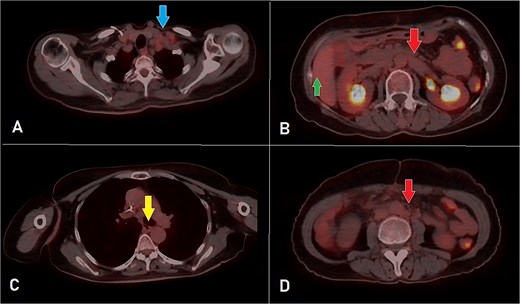

A computed tomography (CT) scan was performed, and the patient underwent a right hemicolectomy using a laparoscopic-assisted approach, with en bloc resection of the tumor and lymphadenectomy. The procedure was uneventful, with no intraoperative complications, and the patient had an unremarkable immediate postoperative recovery. The staging was determined as T4bN2bMx. Further imaging revealed enlarged mediastinal, supraclavicular, and retroperitoneal lymph nodes, with a solitary liver lesion (Fig. 1). A biopsy from the supraclavicular node indicated moderately differentiated adenocarcinoma of gastrointestinal origin. Molecular profiling showed wild-type RAS, intact MSI, mutant BRAF, and HER2 negative. The patient was started on capecitabine-oxaliplatin (CapeOX) with bevacizumab and completed 11 cycles with a marked clinical and radiological response (Fig. 2).

PET-CT scan (A) showing matted intensely hyper-metabolic left supraclavicular lymph nodes (arrow); (B) demonstrating intensely hyper-metabolic retroperitoneal lymph nodes (inferiorly pointing arrow) and a hyper-metabolic solitary hepatic lesion (superiorly pointing arrow); (C) demonstrating an intensely hyper metabolic mediastinal (para- oesophageal – station VIII) lymph node (arrow); and (D) revealing a few intensely hyper-metabolic retroperitoneal lymph nodes (arrow).